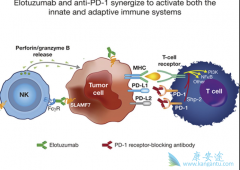

PD-1 抑制剂的诞生,确实为肿瘤医学的进步带来了巨大的跨越;它实现了横跨多个癌种的突破性进展;部分晚期患者实现了长期生存,可以说在现代抗肿瘤的拉锯战中取得了惊人的成绩,医学研究者们认为:免疫治疗将会是未来对抗癌症的主要方向之一。 那么 ...

最近几年, PD-1 抑制剂(PD-1抗体、PD-L1抗体)一路高歌猛进。截止到目前,PD-1抗体、PD-L1抗体、CTLA-4抗体等肿瘤免疫治疗新药,单独使用或者与其他治疗联合使用,已经被批准用于恶性黑色素瘤、非小细胞肺癌、胃癌、肝癌等所有微卫星高度不稳定的实体 ...

近年来,在肿瘤治疗领域最被寄予厚望的当属免疫疗法。肿瘤免疫治疗是利用人体的免疫机制,通过主动或被动的方法来增强患者免疫功能,达到杀伤肿瘤细胞的目的。医学界普遍认为,肿瘤免疫治疗在继手术、化疗、放疗、靶向治疗后将为肿瘤治疗领域带来一场全 ...